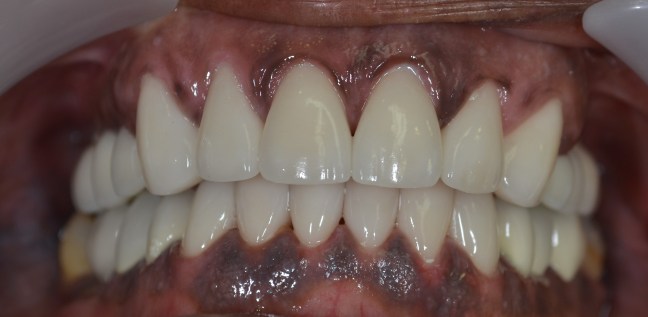

Funkcionális és esztétikai kezelés: harapás korrigálása a fogív kiegyenesítése, fogak közötti rések szűkítése, kereszt harapás megszüntetése az összes megmaradt fog koronázásával. A hiányzó hátsó fogak pótlása implantátumokon megtámasztott koronákkal.

Protetikai munka elkészülésének ideje: 10 munkanap

Koronák anyaga: fémkerámia

Fogszín: A1.